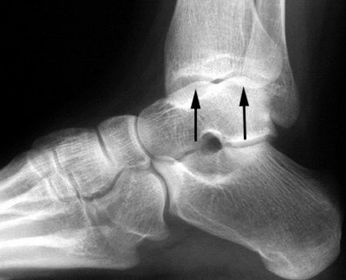

| What is this? What is shown by A and B? | STJ coalition A = talar neck spurring B = Halo or 'C' sign |

| What is this? | Posterior talocalcaneal coalition |